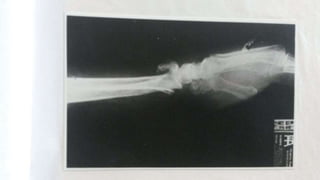

RADIOGRAFÍA RADIO CON CALLO

ÓSEO EN FORMACIÓN

Remodelación, porciones muertas del callo óseo son eliminadas,

hueso compacto aparece, reorganización del hueso mineralizado, la

estructura final es similar al hueso original pero puede

estar mas engrosada.